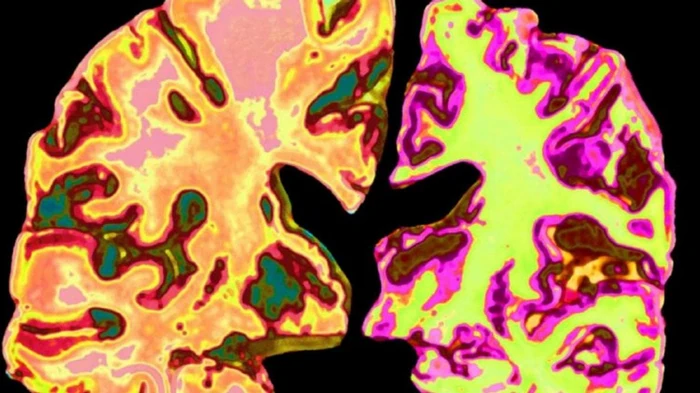

![]() Фото: Getty Images Исследование показало, что добавка лития омолаживает мозг и восстанавливает память

Ученые выяснили, что литий может помогать при болезни Альцгеймера. Он способствует улучшению памяти, восстанавливает работу мозга и помогает расщеплять белковые бляшки, которые провоцируют развитие атеросклероза и деменции. Это открытие может стать основой новых способов лечения. Об этом свидетельствуют результаты исследования, опубликованные в журнале Nature. Результаты семилетней работы ученых из Гарвардской медицинской школы показали, что снижение уровня лития в мозге может способствовать развитию болезни Альцгеймера. Исследование показало, что измерение уровня лития может помочь выявить болезнь Альцгеймера за несколько лет до появления первых симптомов. По словам руководителя исследования Брюса Янкнера, это можно сделать, анализируя спинномозговую жидкость, кровь или с помощью визуализации мозга. В здоровом мозге литий помогает нейронам взаимодействовать между собой, поддерживая связи и каналы между ними. Он также способствует образованию миелина — защитной оболочки, покрывающей эти каналы. Кроме того, литий помогает специальным клеткам мозга — микроглии — очищать мозг от остатков, которые могут мешать его работе.

Зато недостаток лития в мозге связан с ухудшением состояния при болезни Альцгеймера у мышей. Когда лития в мозге становится меньше, ускоряется образование вредных белковых скоплений, мешающих нервным клеткам «общаться» между собой — именно это и происходит у больных Альцгеймером. Сами бляшки также оттягивают литий, уменьшая его способность помогать мозгу. Кроме того, недостаток лития усугубляет состояние синапсов, повреждает миелин (который защищает нервные волокна), и снижает способность микроглии — «убирающих» клеток в мозге — расщеплять эти бляшки. Хотя лития в мозге очень мало, он выполняет немаловажную функцию. Команда Янкнера исследовала более 500 образцов человеческого мозга и обнаружила, что естественный уровень лития в этом органе в тысячу раз ниже, чем в лекарствах, которые дают пациентам с биполярным расстройством. Команда Янкнера исследовала, что ограничение лития в питании вызывает потерю памяти и синапсов у мышей. «Когда мы давали мышам оротат лития (пищевую добавку на основе лития — ред.), их память возвращалась к уровню молодых, шестимесячных животных», — рассказал Янкнер. Оротат лития помог мышам снизить образование вредных белковых бляшек (амилоида) и клубочков тау, а также улучшил способность микроглиальных клеток очищать мозг от этих бляшек. Таким образом, исследователи смогли остановить развитие болезни у мышей и восстановить работу их мозга, используя литий оротат в очень малых дозах — достаточных для того, чтобы воссоздать естественный уровень этого металла в мозге.